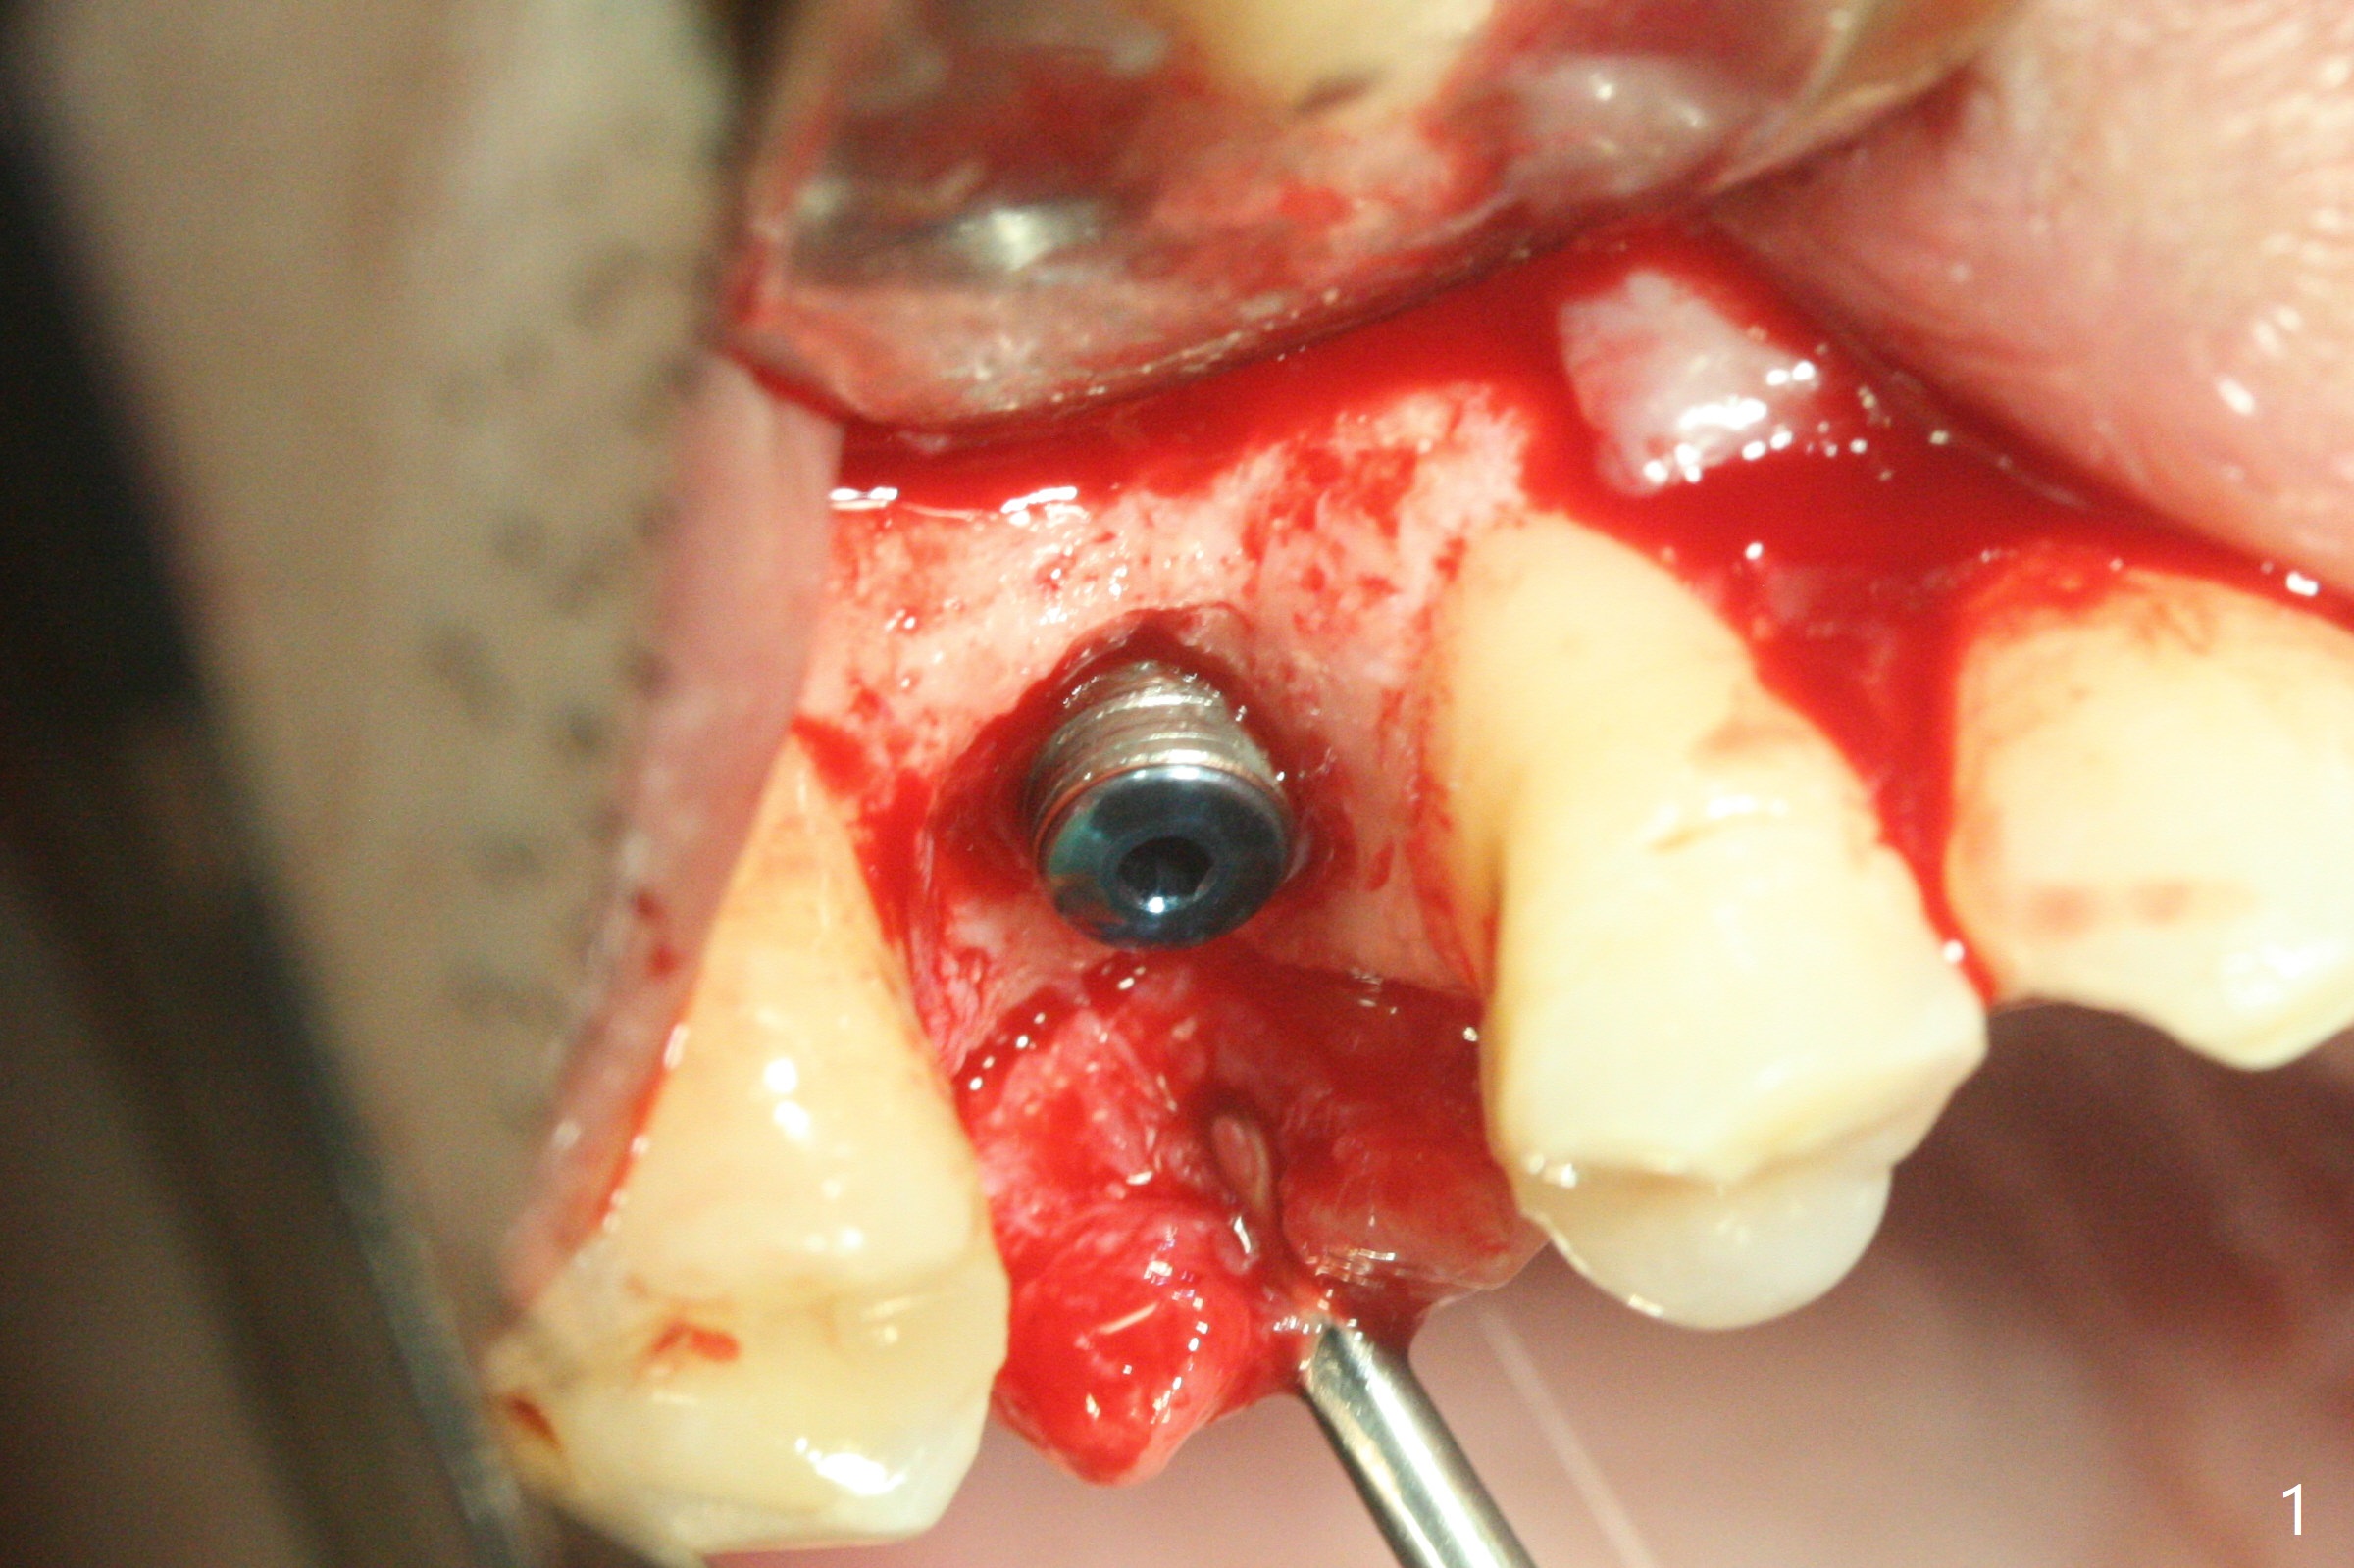

尽管没有任何症状,右上5牙冠粘固后2年5个月,牙冠与基台取出(没有使用扳手,说明基台未完全就位),切开,去除少量肉芽组织,仍然发现植体螺纹暴露(图一),使用一种叫I Brush 钛合金刷子清洁后,放置粘性骨块(图二: S),它坐在牙槽嵴上仿佛非常安稳,多么象马鞍(Saddle)。覆盖一张PRF膜和一小张Cytoplast(不可吸收膜,Osteogenics (company) 图三:箭头),使用PTFE缝线(与Cytoplast同样一种材料)缝合。术后即刻根尖片显示骨粉服服帖帖地坐落在植体和牙槽嵴上(图四:*)。最后覆盖牙周敷料。后者术后十天左右脱落,伤口愈合正常,颊侧瘘道仿佛消失,颊侧骨壁好像不再凹陷了(图五,六)。术后5周,膜已经脱落,缝线撤除后,伤口好像二期愈合,但愿肉芽组织下面骨粉尚未损失太多。术后三个月根尖片显示骨粉减少(图八)。不可吸收膜脱落可能造成骨粉流失。应该做减张缝合。术后4.5个月颊侧骨壁又凹陷(图九:箭头,需要decortication),但是uncover时植体周围都有骨质包绕,术后咬翼片也证明近中,远中骨质接触植体(图十:由于找不到合适愈合基台,直接放置基台和牙冠)。粘固后2.5个月虽然颊侧骨板凹陷,但是没有植体周围炎迹象(图十一)。